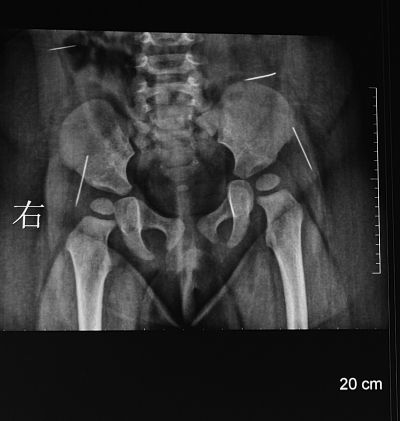

“一根、兩根、三根、四根,這是右側(cè)腰部一根,這是左側(cè)腰部,這是臀部的,像縫衣針,還有像大頭針,三厘米,臀部這兩根很長,腰上兩根1.5厘米差不多……”淮安市婦幼保健院手術(shù)醫(yī)生夏順林拿著女嬰的X片向記者介紹。